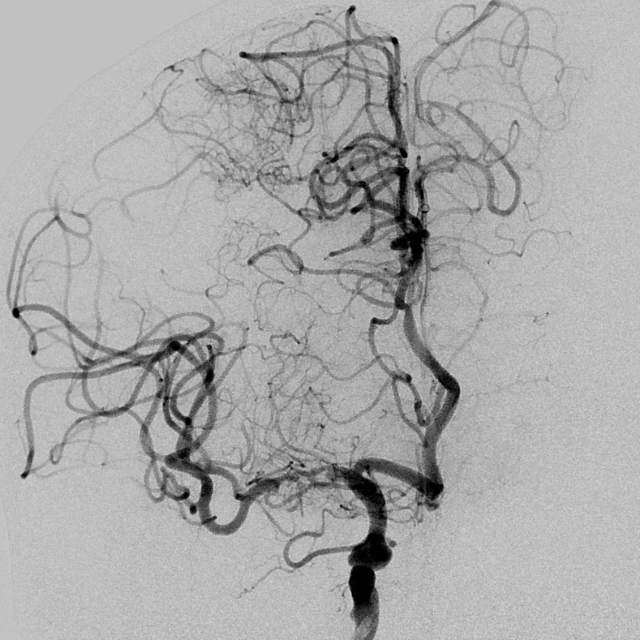

78岁老年男性,最近一个半月来已经和家里人没法正常交流,认知能力大幅下降,在农村,可能也就认为年龄大了,听天由命了。可老人家就是福大命大,有亲戚做医生,间隔17天先后为老人做了两次头颅MRI,发现脑梗塞,右侧血管长节段严重狭窄,右侧大脑半球缺血严重(图6,满江红),手术风险大……,家属经过反复咨询、犹豫、权衡,选择了保守治疗,毕竟老人年龄大了,手腿现在还能动,手术也有风险,时机也不是太好,国外研究不推荐,国内研究也不支持,保守治疗似乎是个不错的选择。然而,保守期间,患者反复出现脑梗塞,认知能力进行性下降,最终促使家属决定采用外科干预。然而,对医生而言,在梗塞的急性期处理这种长节段密布分支血管的病变风险不言而喻,而一味的观望和等候肯定不是最佳选择。过一点,可能出血;欠一点,可能闭塞。全面认真评估后,我们顺利为老人家完成了I期治疗,老人家的“火焰山”(图6)变成了“绿油油”充满生机的田野(图14),缺血明显改善,认知能力大幅提高,术后就能和家人正常交流了,也记起了很多以前忘记的事情……,家人很开心。